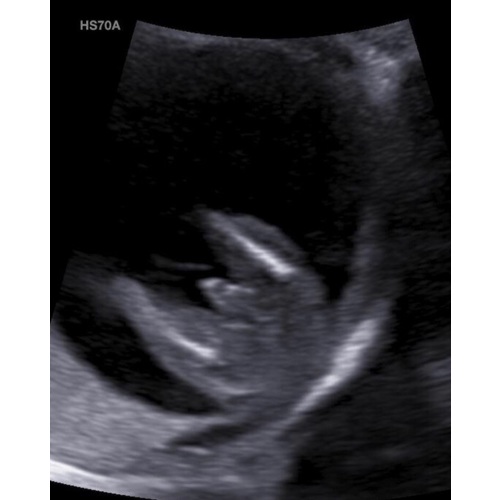

Ik heb helaas geen foto meer van de geslachtsbepaling van onze baby, een jongen.

Maar die lijkt op de foto's van hieronder allemaal.

Maar ik heb de geslachtsbepaling gedaan met 16 weken en wilde met de 20 weken toch nog even zekerheid hebben 😛

Want toen ze de echo via mijn buik deed, zei ze: ik weet bijna zeker dat het een meisje is, maar zal voor de zekerheid toch nog een keer inwendig kijken. En toen was het toch een jongen. En het is nog steeds een jongen 😂

Maar ze zei ook dat ze ons bijna naar huis had gestuurd met "een meisje".